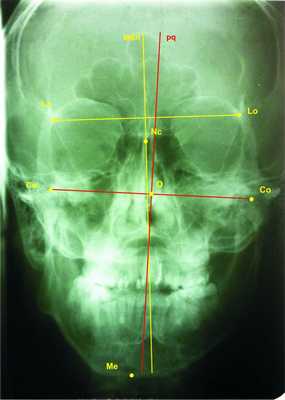

2. Определение цефалометрических точек, необходимых для наших анализов (рис. 1). Рисунок 1. Цефалометрические точки, использующиеся для разработки графических моделей. 2.1. Точка Lo (lateroorbitalae — dextra et sinistra) — пересечение латерального орбитального контура и больших крьльев клиновидной кости [6, 9, 11, 12]. 2.2. Точка Nc — на основе crista galli [6, 11, 12]. 2.3. Точка Co (condilion — dextra et sinistra) — самая высокая точка суставной головки НЧ [6, 9, 11]. 2.4. Точка Ме (mention) — нижняя точка подбородочного симфиза НЧ [6, 11, 12]. 2.5. Точкой О обозначаем середину сегмента Со-Со (см. рис. 1).

3. Построение средней сагиттальной прямой. Средняя сагиттальная прямая (MSR) выбрана методом V. Sassounni [12]: из точки Nc опускаем перпендикуляр к прямой, соединяющей левую и правую точки Lo (рис. 2). Рисунок 2. Средняя сагиттальная прямая (MSR) по V. Sassounni. Этот метод построения базовой линии выбран потому, что клиновидная кость исключительно симметрична и точка Lo — очень хорошая базовая точка для сравнения роста и развития черепа [12].

4. Построение сагиттальной оси НЧ и то, почему оно необходимо, мы объясним ниже. Соединяем уже отмеченные точки Со-Со и из середины полученного таким образом сегмента (точка О) опускаем перпендикуляр, который является сагиттальной осью мандибулы. Обозначим ее pq (рис.3). Рисунок 3. Построение сагиттальной оси НЧ.

Обоснование. Созданная нами методика оценки трансверсальных несоответствий лицевого отдела черепа была продиктована неточностью анализа симметрии НЧ. Является ли НЧ симметричной или нет, обычно определяют по средней сагиттальной оси черепа, но иногда это может ввести в заблуждение. Например, НЧ может быть симметричной, но при ротации в суставах точка Ме перемещается с лицевой оси MSR, что позволяет сделать неверный вывод об асимметричности НЧ. Мы рассматриваем НЧ в качестве отдельного объекта, имеющего свою собственную сагиттальную ось (pq), так как нельзя определять симметричность одного тела (НЧ) относительно сагиттальной оси другого тела (черепа): это приводит к 2 системам координат: 1 — черепа (MSR по V. Sassounni), другая — НЧ (pq) (рис. 5, см. на цв. вклейке). Рисунок 5. Компьютерная графика 2 сагиттальных осей MSR и pq.